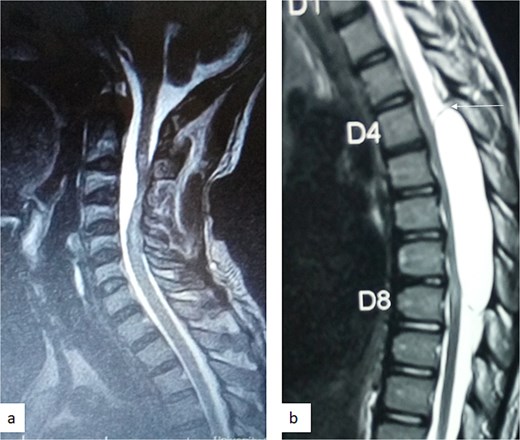

A 47-year-old man presented to us with progressive weakness of the extremities of 5 weeks duration. The weakness was first noticed in the left hand and progressed to involve the entire left upper limb and subsequently the right upper limb and the lower limbs. There was associated paraesthesia, constipation, and erectile dysfunction. Clinical examination revealed a middle-aged man with spastic quadriplegia and exaggerated muscle stretch reflexes. The sensory level was C4. Other systemic examination findings were normal. A clinical diagnosis of C4 non-traumatic myelopathy, Frankel B was made. Cervical spine MRI showed an intradural-extramedullary lesion with similar intensities to cerebrospinal fluid (CSF) on all sequences anterior to the spinal cord at C2–C4 with significant cord compression at C3–C4 and cord signal change on T2-weighted image at C2–C5 (Fig. 1). A diagnosis of cervical spine intradural AC was made. The lesion was accessed through C3–C4 laminectomies. At surgery, there was a cyst anterior to the cord with the latter flattened and displaced posteriorly. The cyst was excised completely and water tight dura closure done (Fig. 2). He made progressive post-operative neurological improvement and he was discharged on the 10th post-operative day. He was last seen 22 months post-surgery. At the time, he was ambulating without support, power was Grade 4+ to 5 in the upper and lower limbs.

Sagittal T1-weighted (a) and T2-weighted (b) cervical spine MRI images showing an intradural arachnoid cyst posteriorly displacing and compressing the spinal cord.

MRI is the imaging modality of choice for the diagnosis and follow-up of SACs [4]. It does not require intrathecal injection of contrast and demonstrates the location, size, extent, and nature of the cysts as well as neural elements compression and intrinsic cord changes among other features [7, 16–18]. On MRI SACs have similar signal intensities to those of CSF, hypointense on T1-weighted, and hyperintense on T2-weighted images [16]. Extradural cysts may show absent posterior epidural fat, epidural fat capping, and T2-hypointense cyst wall [16, 19, 20] (Figs 3 and 6b). Intradural cysts are characterized by widening of the subarachnoid space, displacement of the cord/cord compression and an undistinguishable cyst wall [2, 21] (Fig. 1). The site of communication between the cysts and subarachnoid may not be demonstrable on MRI [16]. Computed tomography myelograghy has been the imaging of choice in demonstrating the communicating site between the cyst and the subarachnoid cyst [16]. Newer MRI flow studies using cinematic MRI has proven to also be able to demonstrate the communication site [22].

(a) Sagittal T2-weighted cervical spine MRI image showing expanded subarachnoid space anterior to the spinal cord at C2–C4, posterior displacement and compression of the cord and cord signal change at C2–C5. The wall of the cyst is indistinguishable suggestive of intradural spinal arachnoid cyst. (b) Sagittal T2-weighted thoracic MRI image showing compression of the spinal cord anteriorly. There is visible hypointense cyst wall (arrow) suggestive of extradural cyst.